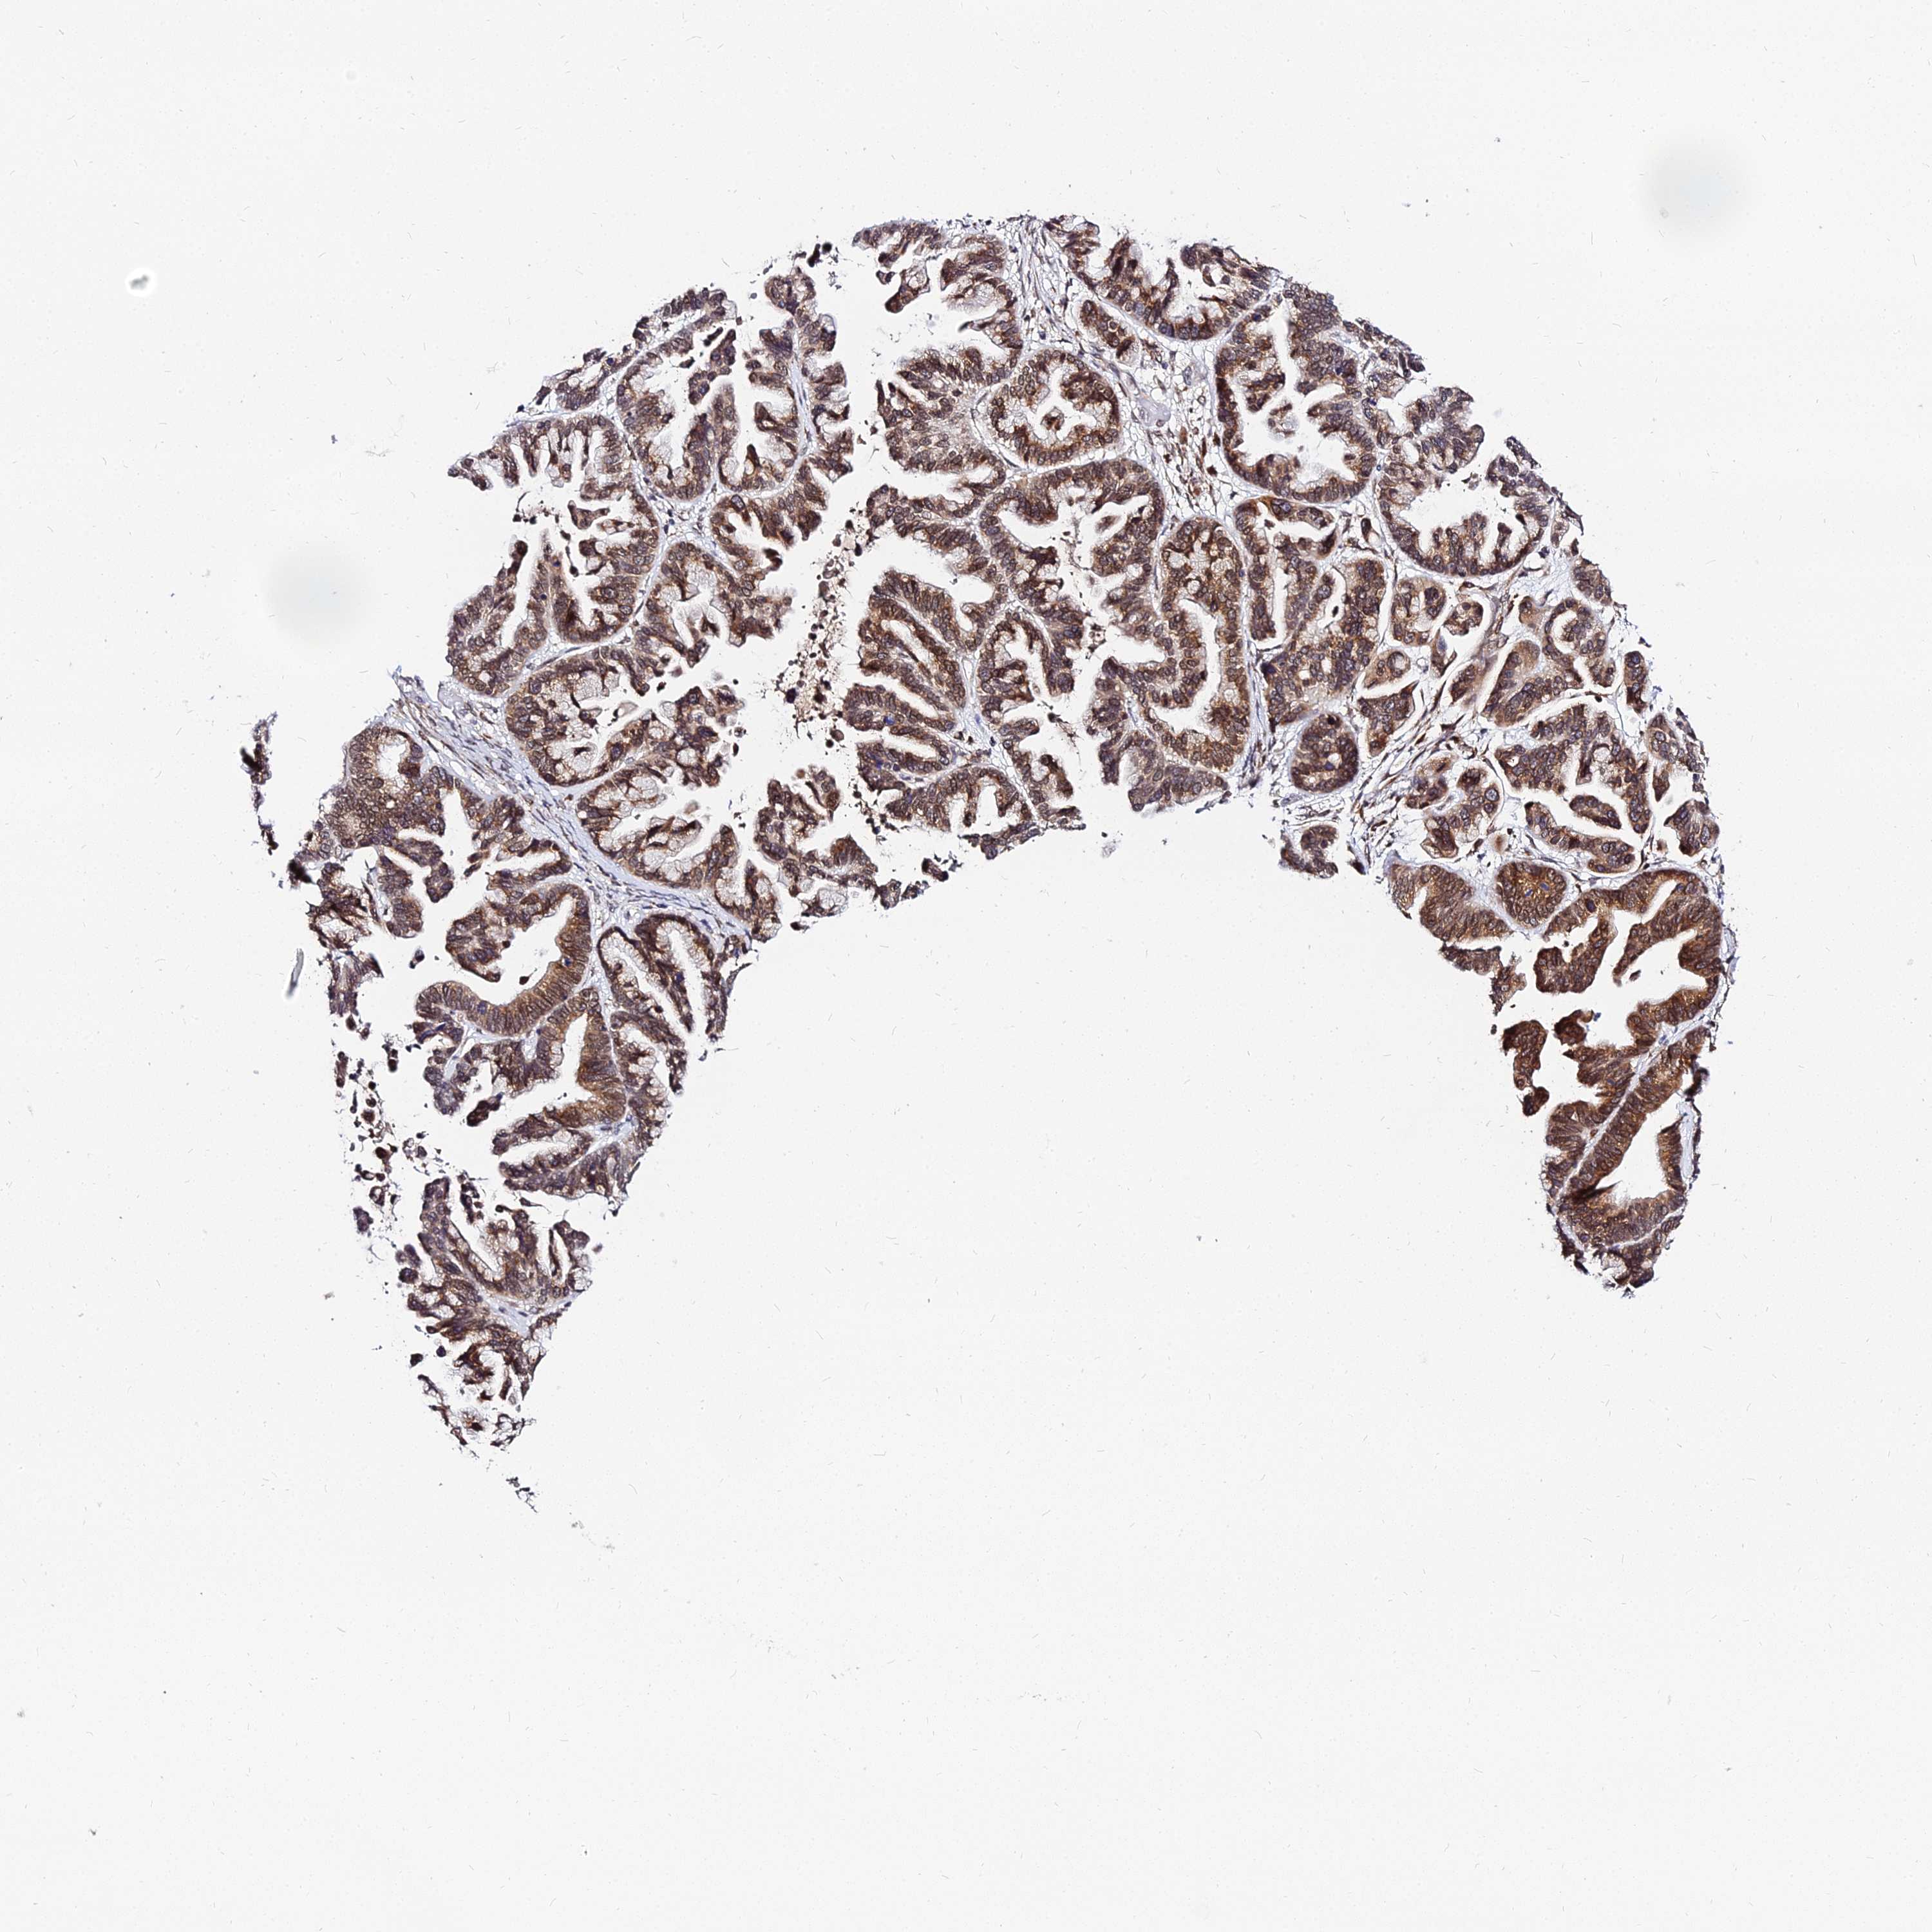

OVARIAN CANCER - Protein expressioni

A mouse-over function shows sample information and annotation data. Click on an image to view it in a full screen mode. Samples can be filtered based on level of antibody staining by selecting one or several of the following categories: high, medium, low and not detected. The assay and annotation is described here.

Note that samples used for immunohistochemistry by the Human Protein Atlas do not correspond to samples in the TCGA dataset.

Antibody stainingi

Antibody staining in the annotated cell types in the current human tissue is reported as not detected, low, medium, or high, based on conventional immunohistochemistry profiling in selected tissues. This score is based on the combination of the staining intensity and fraction of stained cells.

Each image is clickable and will lead to virtual microscopy that enables deeper exploration of all samples and also displays staining intensity scores, fraction scores and subcellular localization as well as patient and tissue information for each sample.

Antibody HPA046041

Staining

High

Medium

Low

Not detected

Intensity

Strong

Moderate

Weak

Negative

Quantity

>75%

75%-25%

<25%

None

Location

Nuclear

Cytoplasmic/membranous

Cytoplasmic/membranous,nuclear

Cystadenocarcinoma, serous, NOS

Carcinoma, NOS

Cystadenocarcinoma, mucinous, NOS

Carcinoma, endometroid